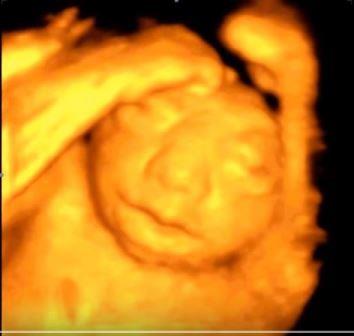

Dopo la 12a settimana per il diretto contatto col liquido amniotico ed i traumi determinati dal contatto con la parete uterina l'encefalo si trasforma in una massa di tessuto molle aderente alla base del cranio determinandosi il quadro dell'anencefalia caratterizzato dall'assenza della volta cranica e da tessuto cerebrale scarsamente rappresentato.

In sezione coronale, per la presenza di macroftalmia, l'estremo cefalico assume il tipico aspetto "a rana".